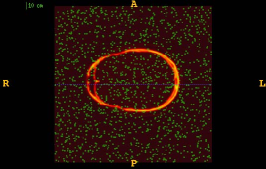

Figure 1 shows the examples of pixel selection masks generated using tested approaches at the highest resolution level for pixel sampling rate 0.5%. It is obvious that the samples generated with the URS approach are extremely spread, whereas the samples generated with the GMS approach are overly concentrated along the gradient magnitude structures present in the image. The proposed approach produces samples that balance those two extremities.